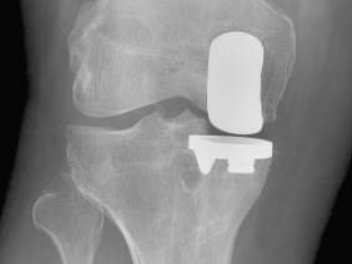

Qu'est-ce qu'une Prothèse uni-compartimentale de Genou?

Cette intervention consiste à remplacer une partie de l’articulation du genou, le compartiment fémoro-tibial interne ou externe, par des composants artificiels qui reproduisent l’anatomie initiale du genou. Le type d’implant doit être adapté à chaque cas particulier, en ce qui concerne sa forme, sa taille, la nature des matériaux entrant dans sa composition, son revêtement extérieur et la technique chirurgicale à employer.

Généralement, une prothèse de genou se divise en deux parties : un insert fémoral et une embase tibiale surmontée d’un polyéthylène. Les composants sont généralement fixés par du ciment.

Album photo